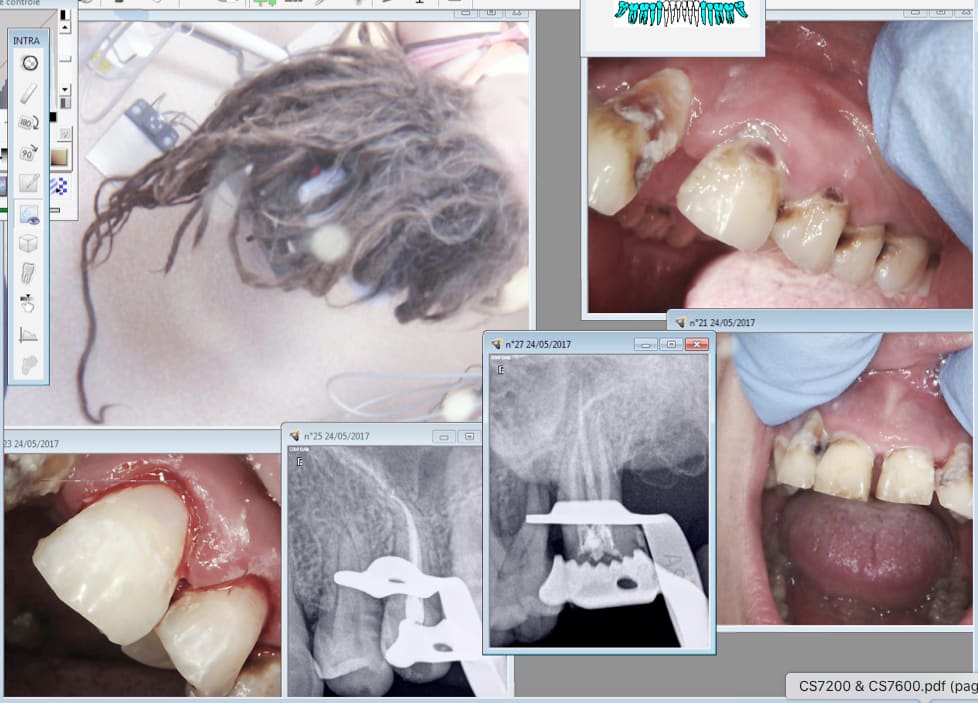

Pour cette patiente par exemple....... La sécu paye mais se fait rembourser par le fonds CMU.

Et par moi qui accepte de lui faire des soins de qualité pour un tarif de merde. Tu penses bien que je ne gagne pas grand chose sur ces soins opposables, non ? Qui me rembourse moi sur ces soins réalisés à perte ? Hein ?

Ca va passer en se rattrapant sur la prothèse des patients solvables , qui financent le fond CMU via l'impôt, qui me font passer pour un escroc ?